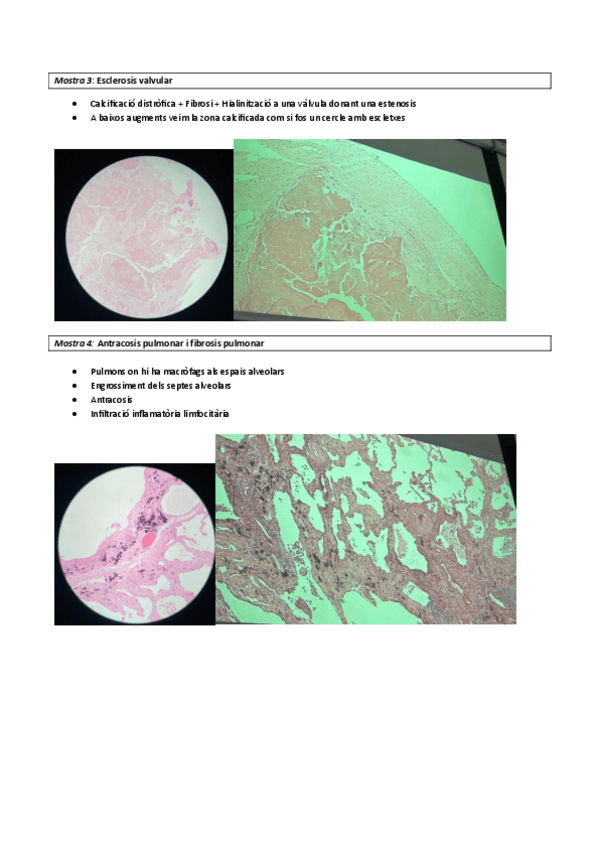

He publicado nuevos practicas de 3º Anatomia Patològica Especial: MICROSCOPIS.pdf

21 páginas